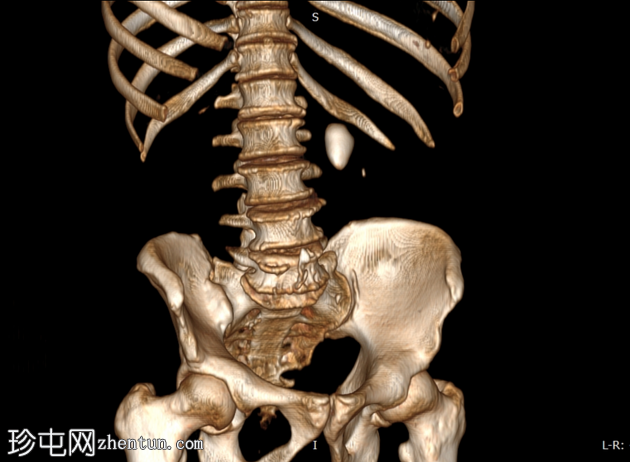

三维

重建

三维重建图像更清晰地显示了钙化结石;然而,需警惕腹主动脉钙化。